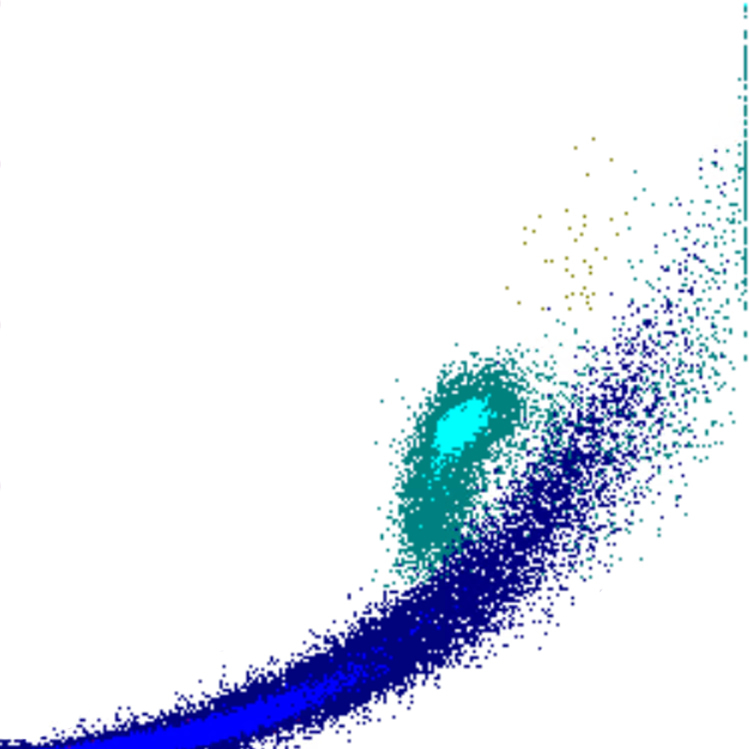

Side Scatter

La complexité cellulaire est principalement déterminée par la présence de structures intracellulaires telles que les granulations. Dans une moindre mesure, la forme du noyau (lobulation) et la présence de vacuoles jouent également un rôle. Dans le canal WDF du Sysmex, les éosinophiles présentent un SSC plus élevé que la normale en raison de l’effet du réactif sur leur granulation.

SSC scatter

SSC faible

SSC élevé